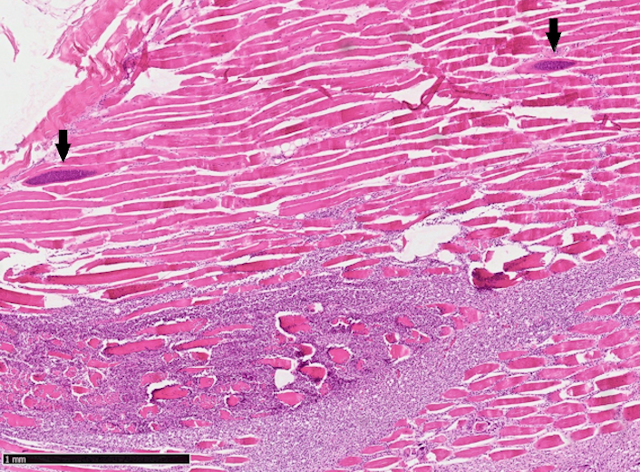

Die Muskelproben wurden kulturell auf bakterielle Infektionserreger untersucht, jedoch mit negativem Ergebnis. Parallel dazu wurden die Muskulatur feingeweblich (histologisch) untersucht. Das histologische Bild der Muskelfleischproben zeigte eine starke Einwanderung von Entzündungszellen in das Gewebe mit Zelluntergängen (Nekrose) und einem massiven Befall mit Sarkosporidienzysten in diesen Bereichen.

Abbildung 2: Reh. Histologische Untersuchung der Muskelfleischprobe: Übersicht Skelettmuskulatur mit Einwanderung von Entzündungszellen und Nekrose (Kreis)

Abbildung 3: Reh. Histologische Untersuchung der Muskelfleischprobe: Nahansicht Skelettmuskulatur mit Entzündung und Sarkosporidienzysten (Pfeile)

In der Entzündungsreaktion lag ein hoher Anteil von spezialisierten weißen Blutkörperchen vor - den eosinophilen Granulozyten. Diese spielen als Teil des Immunsystems bei der Abwehr von Parasiten eine bedeutende Rolle. Das vorliegende Erkrankungsbild wurde als eosinophile Myositis verursacht durch Sarkosporidien diagnostiziert. Die Grünverfärbung der Muskulatur ist durch die enzymatische Zerstörung des Muskelgewebes durch die eosinophilen Granulozyten und die Bildung von biologischen Abbauprodukten zu erklären.